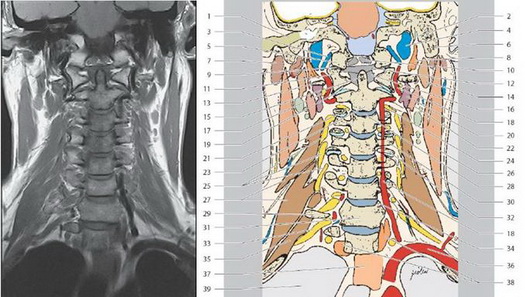

Секционная анатомия позвоночника

Цветные обозначения позвоночного столба.

МРТ позвоночника

1. Выйная связка

2. Зуб второго шейного позвонка

3. Выступающий позвонок С 7

4. Тело грудного позвонка Т1

5. Позвоночный канал

6. Грудной отдел спинного мозга

7. Межпозвоночный диск

8. Надостистые связки

9. Подостистые связки

10. Тело поясничного позвонка L1

11. Мозговой конус

12. Конский хвост

13. Остистый отросток

14. Текальная сумка

15. Крестец (S1)

16. Мыс крестца

17. Копчик

МРТ шейного отдела позвоночника

1. Большое затылочное отверстие

2. Трапециевидная мышца(нисходяшая часть)

3. Покровная мембрана

4. Затылочная кость (внутренний затылочный выступ)

5. Передняя атланто-затылочная мембрана

6. Полуостистая мышца головы

7. Верхушечная связка зубовидного отростка

8. Малая дорсальная прямая мышца головы

9. Продольный пучок

10. Задняя атланто-затылочная мембрана

11. Второй шейный позвонок (передняя дуга)

12. Подзатылочная жировая клетчатка

13. Средний атланто-аксиальный сустав

14. Второй шейный позвонок (задняя дуга)

15. Первый шейный позвонок (зубовидный отросток)

16. Глубокие вены шеи

17. Первый шейный позвонок (тело)

18. Поперечная связка первого шейного позвонка

19. Длинная мышца головы

20. Задняя продольная связка

21. Нижняя концевая пластинка

позвонка СЗ

22. Межостистая связка

23. Верхняя концевая пластинка позвонка С4

24. Шейный отдел спинного мозга

25. Передняя продольная связка

26. Субарахноидальное пространство

27. Межпозвоночный диск

28. Межостистые мышцы

29. Пищевод

30. Остистый отросток С7

31. Базально-позвоночные вены

32. Желтая связка

33. Тело грудного позвонка Т1

34. Надостистая связка

35. Позвоночный канал

МРТ – шейный отдел

1. Наружный слуховой канал

2. Шилососцевидное отверстие

3. Позвоночная вена

4. Внутренняя яремная вена

5. Затылочный мыщелок

6. Сосцевидный отросток

7. Околоушная слюнная железа

8. Латеральная прямая мышца головы

9. Атланто-затылочный сустав

10. Покровная мембрана

11. Второй шейный позвонок

12. Поперечная связка

13. Второй шейный позвонок (поперечный отросток)

14. Двубрюшная мышца (заднее брюшко)

15. Второй шейный позвонок (зубовидный отросток)

16. Клиновидные связки

17. Спинномозговой нерв С2

18. Позвоночная артерия

19. Латеральный атлантоаксиальный сустав

20. Нижняя косая мышца головы

21. Межпозвонковый сустав

22. Мышца поднимающая лопатку

23. Первый шейный позвонок (тело)

24. Спинномозговой узел СЗ

25. Шейное сплетение

26. Грудиноключичнососцевидная мышца

27. Средняя лестничная мышца

28. Межпозвоночный диск (С2/СЗ)

29. Поперечный отросток С7

30. Верхний суставной отросток С4

31. Тело шейного позвонка С7

32. Нижний суставной отросток

33. Спинномозговой нерв С8

34. Крючковидный отросток С7

35. Задняя лестничная мышца

36. Подключичная артерия

37. Пищевод

38. Длинная мышца шеи

39. Легкое